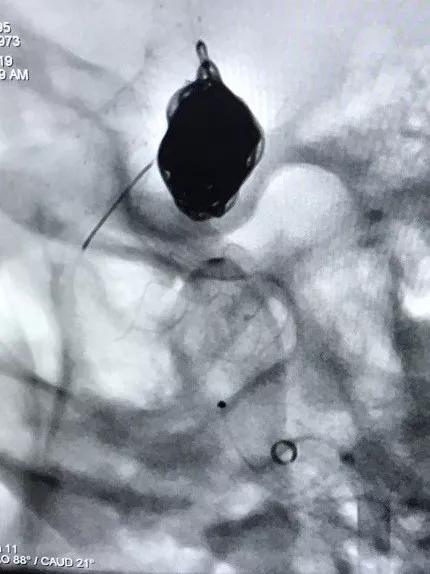

再行右侧颈内动脉血流导向装置置入术:将8F Envoy导引导管置入右侧颈总动脉,105cm 6F Navien导引导管头端置入颈内动脉岩骨段,造影见海绵窦段3个动脉瘤,由近及远直径一次为5mm、8mm、9mm,颈内动脉床突上段可见一大小约为5×4mm的宽颈动脉瘤。

选择4.0×15mm Tubridge®支架,成功释放,覆盖颈内动脉床突上段动脉瘤。

然后再次通过支架并达到右侧大脑中动脉,向海绵窦段多发动脉瘤输送并释放4.0×30mm Tubridge®支架。

▲各角度观察显示Tubridge®贴壁良好